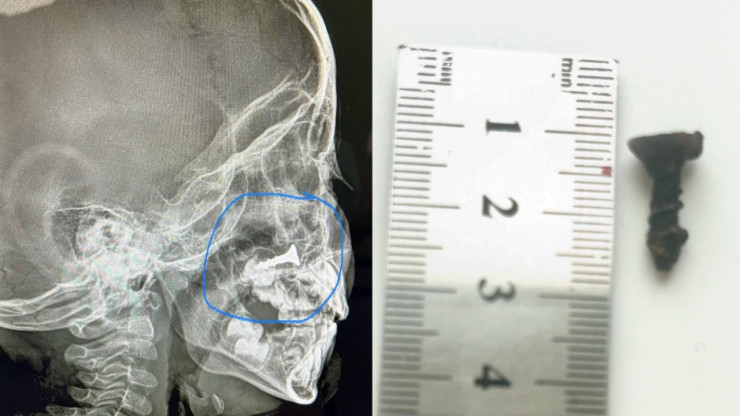

5. Ребенок полгода жил с шурупом в носу на юге Казахстана

Врачи областной многопрофильной детской больницы извлекли из носа малыша шуруп. Он находился в носовой полости полгода. Как рассказал заведующий отделением экстренной хирургии областной многопрофильной детской больницы Болат Маханбетияров, инородное тело обнаружили случайно, когда мама привела ребенка на рентген.

Фотографии предоставлены врачами областной многопрофильной детской больницы Кызылорды